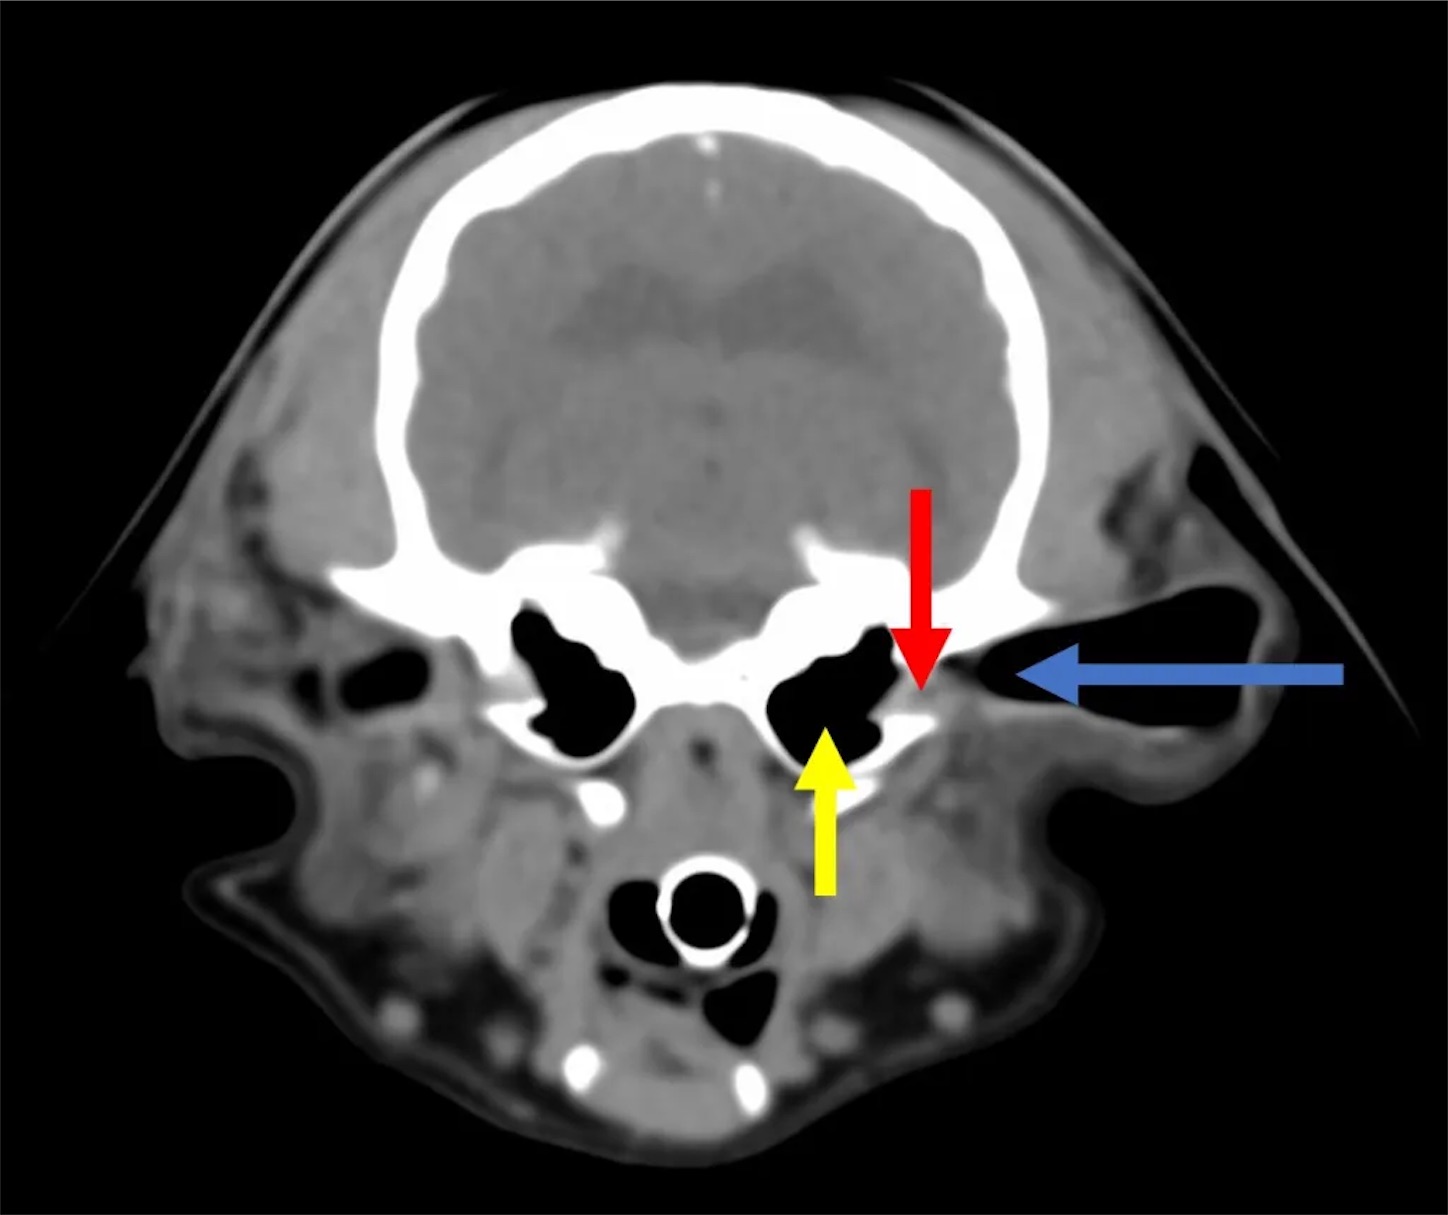

耳の鼓膜の奥の鼓室包黄色い矢印 にばい菌が溜まり神経を

イタズラしているから

眼球が横にグラグラゆれ

首は右に固り動かない

眼球揺れるからフラフラする

ホルネル症候群 発症

鼓膜無くなってたから チューブ入れて鼓室包の膿を抽出 消毒